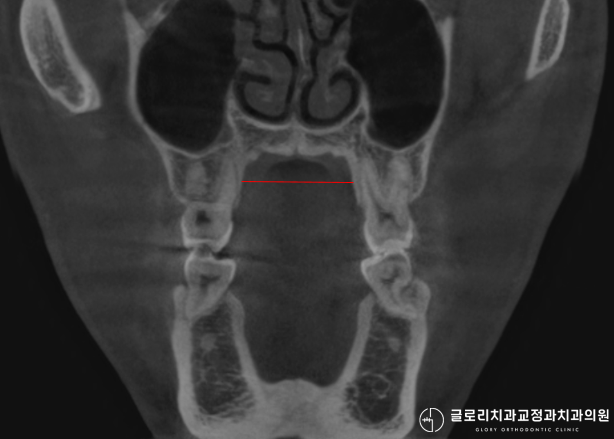

또한 턱관절에 무리가 가서 통증이 나타나거나 입을 벌릴 때 소리가 나는 증상이 생길 수 있기 때문에 사전에 턱관절 검사도 필수적으로 진행합니다.

이때 정밀 검사를 통해 발치 필요 여부를 신중하게 판단합니다.

또한 치아 뿌리가 잇몸뼈 바깥으로 밀려나는 치근 노출 위험도 고려해야 합니다.